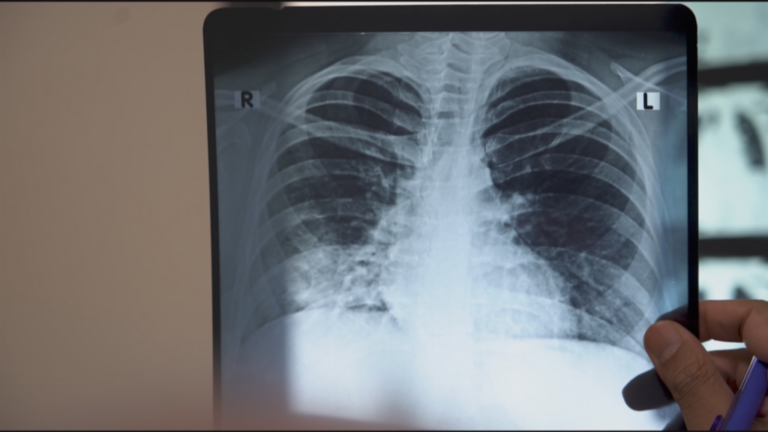

In 2018, Indian Prime Minister Narendra Modi promised to eradicate tuberculosis (TB) in the country by 2025, aiming to set an example globally. Since December 2024, India’s health minister has led a “100-day campaign” to eliminate TB, but recent WHO data shows India is far from its goal. It recorded 2.5 to 3 million new cases and over 400,000 deaths in 2023 alone, accounting for a third of global TB cases and deaths. The country faces two major issues: TB treatment shortages and the rise of multi-drug-resistant TB. While treatments exist, the government’s slow approval of their distribution has hindered progress, leaving India at a critical juncture in its fight against the disease. FRANCE 24’s Khansa Juned and Alban Alvarez report.